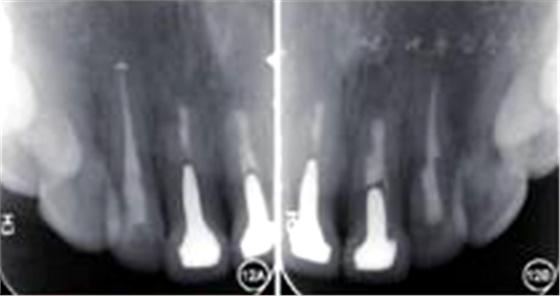

见图12,图13。临床检查叩诊正常,不松动,牙龈色泽正常,切口位置可见隐约瘢痕。根尖X线片显示根尖无明显病变。

图12 术后2年复查患者根尖X线片 A:根尖无明显病变;B:根尖无明显病变